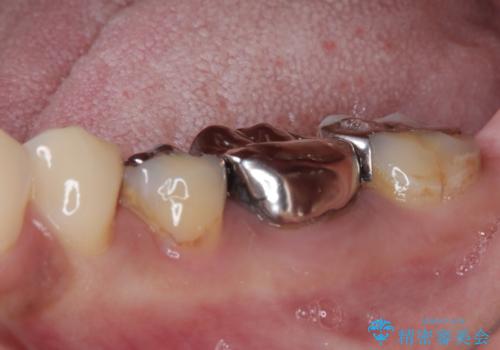

- 銀歯の奥が欠けてしまったとのことで来院された患者様です。

大きな銀歯が装着されており、その下からむし歯が広がっている状態でした。

特に症状はなく、神経組織も健全な状態であったため、むし歯を全て取り切った後にフルジルコニアクラウンにて補綴することとしました。